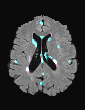

In recent years, data-driven machine learning (ML) methods have revolutionized the computer vision community by providing novel efficient solutions to many unsolved (medical) image analysis problems. However, due to the increasing privacy concerns and data fragmentation on many different sites, existing medical data are not fully utilized, thus limiting the potential of ML. Federated learning (FL) enables multiple parties to collaboratively train a ML model without exchanging local data. However, data heterogeneity (non-IID) among the distributed clients is yet a challenge. To this end, we propose a novel federated method, denoted Federated Disentanglement (FedDis), to disentangle the parameter space into shape and appearance, and only share the shape parameter with the clients. FedDis is based on the assumption that the anatomical structure in brain MRI images is similar across multiple institutions, and sharing the shape knowledge would be beneficial in anomaly detection. In this paper, we leverage healthy brain scans of 623 subjects from multiple sites with real data (OASIS, ADNI) in a privacy-preserving fashion to learn a model of normal anatomy, that allows to segment abnormal structures. We demonstrate a superior performance of FedDis on real pathological databases containing 109 subjects; two publicly available MS Lesions (MSLUB, MSISBI), and an in-house database with MS and Glioblastoma (MSI and GBI). FedDis achieved an average dice performance of 0.38, outperforming the state-of-the-art (SOTA) auto-encoder by 42% and the SOTA federated method by 11%. Further, we illustrate that FedDis learns a shape embedding that is orthogonal to the appearance and consistent under different intensity augmentations.